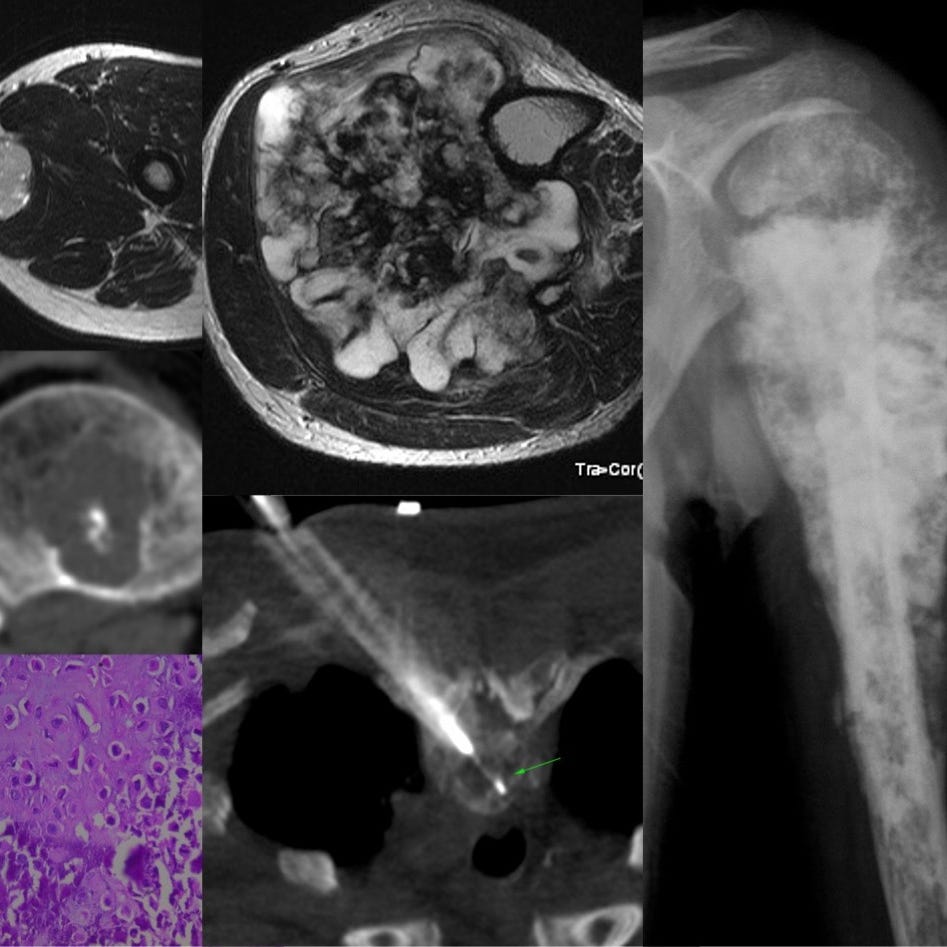

Bone and soft tissue neoplasms - diagnosis and understanding

Radiologist